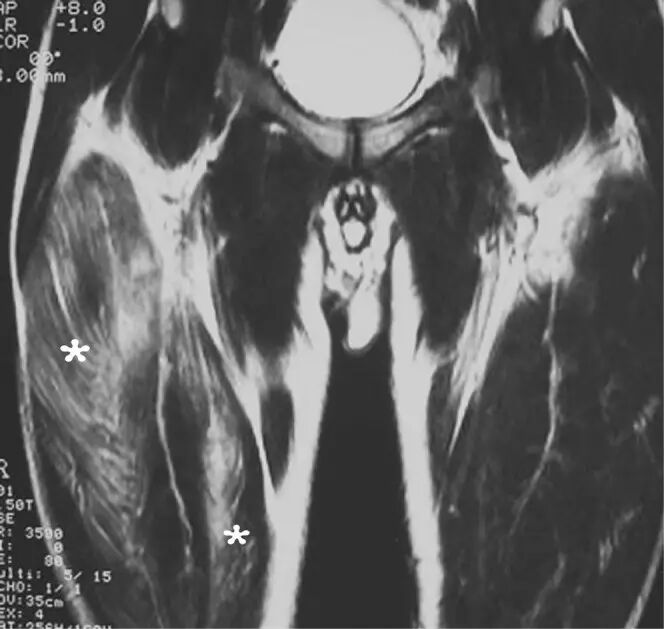

图9.57岁男性特发性肌炎,突然发病的肌肉无力,压痛和无法行走。 冠状短翻转恢复MR图像显示通过骨盆,髋和大腿的大腿肌肉的弥漫性水肿。 肌肉活检揭示“非特异性”肌炎。 症状在6个月的时间内消退,患者能够恢复全身体力活动。

![]()